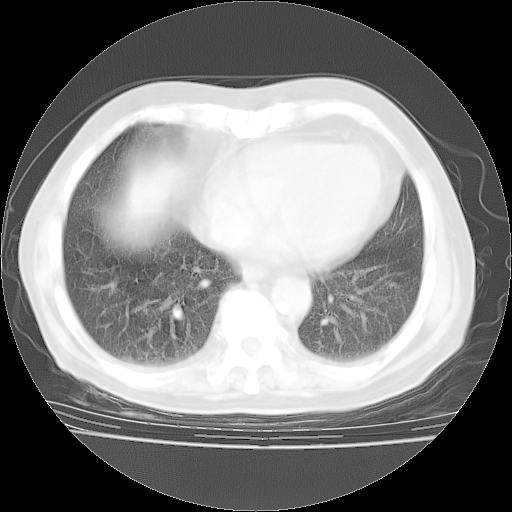

4月28日肺部CT——再次出现类似去年5月9日——透光度降低,“间质性”改变。

4月28日肺部CT——再次出现类似去年5月9日——磨玻璃样、间有“粟粒样”改变。

4月28日肺部CT